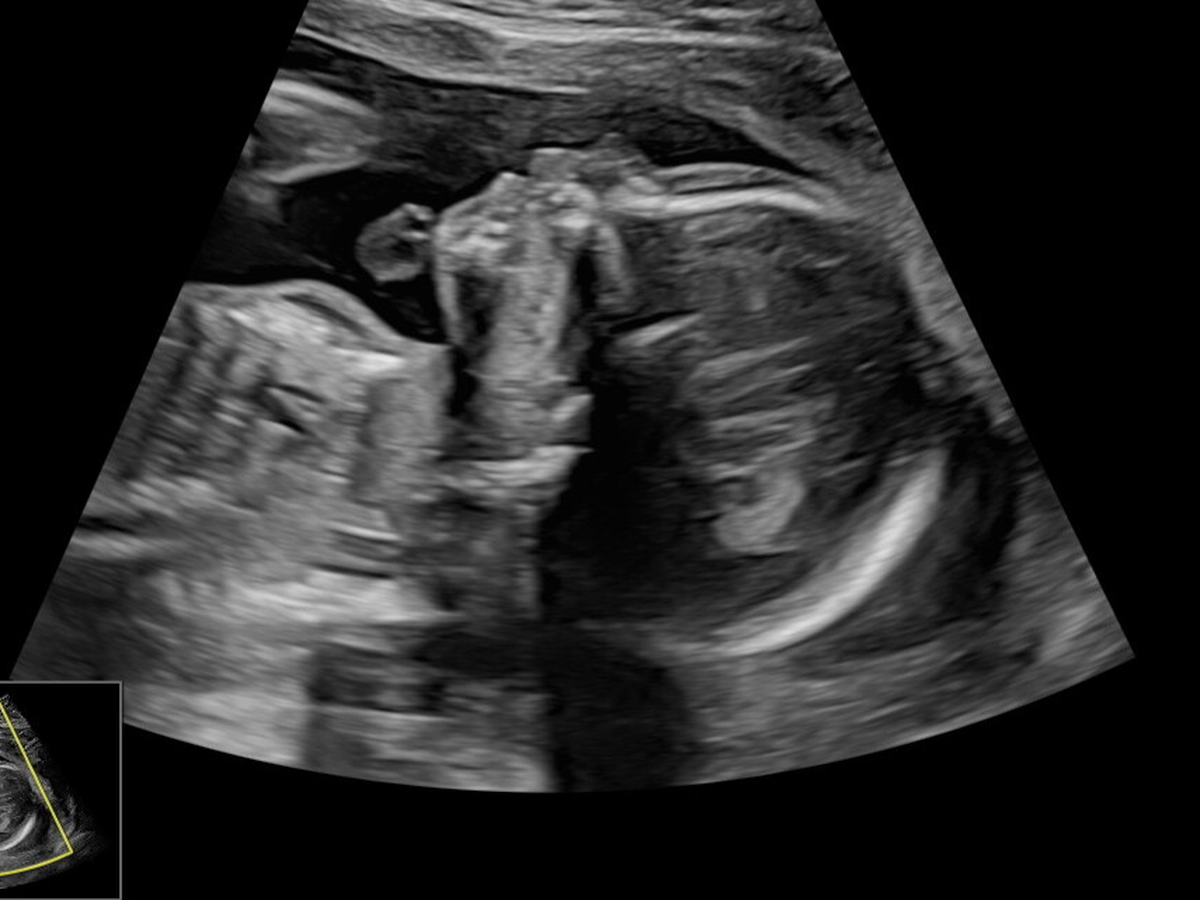

During this pregnancy, we learned that our baby has a severe congenital heart defect (Critical Aortic Stenosis.) Since that diagnosis, our lives have been turned upside down. We are facing constant appointments, repeated fetal echocardiograms, specialist consultations, and the reality that we must travel out of state for advanced fetal cardiac care.

There is a possibility of fetal heart intervention before birth, a procedure that carries significant risks — including the chance that it could be fatal to the baby. Every step forward comes with fear, uncertainty, and decisions no parent should have to make.